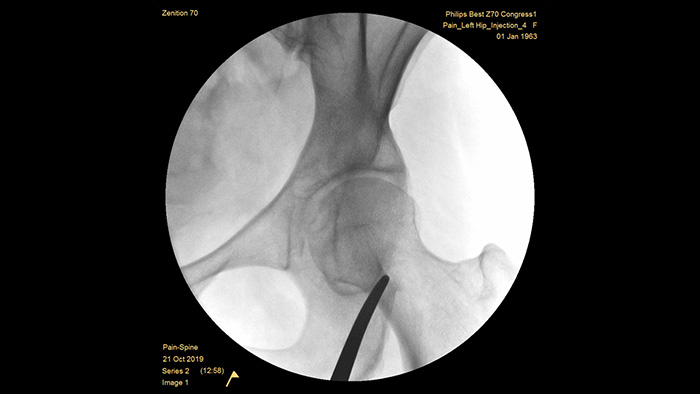

A Philips construiu uma reputação de excelência em termos de eficiência de imagem e dose ao longo de meio século de experiência no desenvolvimento de sistemas de arco em C móvel para o ambiente cirúrgico. As nossas soluções de cirurgia móvel Zenition são baseadas numa abordagem abrangente à gestão das doses. Proporciona uma qualidade de imagem clinicamente relevante durante os procedimentos de intervenção para aplicações de gestão da dor, ao mesmo tempo que gere de forma eficiente a exposição às radiações dos pacientes e do pessoal médico.

A definição de exames de gestão da dor previamente configurada permite aos utilizadores configurar facilmente o sistema durante os procedimentos de intervenção para gestão da dor.

O MetalSmart exclui automaticamente artefactos metálicos causados por implantes metálicos para fornecer maior qualidade de imagem e controlo eficiente da dose durante procedimentos de dor e pacientes com implantes metálicos, em comparação com sistemas sem exclusão de metais. O BodySmart promove a imagiologia e a eficiência da dose corretas à primeira, adaptando automaticamente o campo de medição à área de interesse.

A altura ideal do arco em C totalmente contrabalançado proporciona um amplo espaço de posicionamento em torno de pacientes obesos e para visualizar a coluna lombar e a anca. Suporta o posicionamento sobre a mesa, mesmo com mesas com uma base grande.